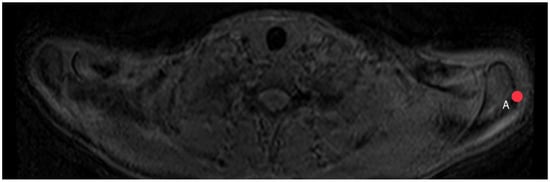

2.5. Acromion Slope (Figure 10)